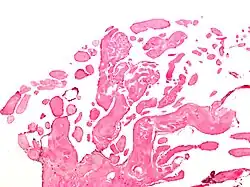

Low magnification micrograph of an excised aortic valve papillary fibroelastoma showing the characteristic avascular branching papillae, H&E stain

Papillary fibroelastoma are typically found and accurately diagnosed by imaging. The diagnosis is confirmed by pathology. Histologically, papillary fibroelastomas have branching avascular papillae, composed of collagen, that are covered by endothelium.